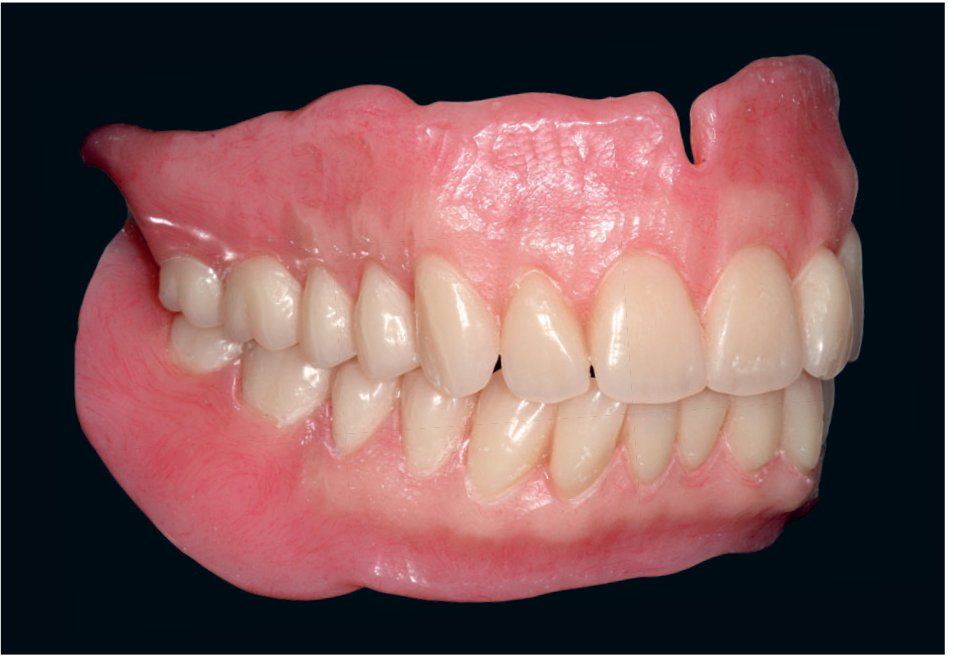

Photos cliniques illustrant des situations d'édentement complet et de passage à l'édentement

Prothèse fixée implantoportée

Utiliser la prothèse amovible d'usage permet de définir dès cette analyse radiographique le type de prothèse qui va être envisagée dans l'hypothèse de la réalisation d'une reconstruction fixe implantoportée. En fonction de l'espace disponible entre le rebord osseux et le bord libre des futures dents prothétiques, trois types de reconstructions seront indiquées selon la classification de Misch :

• dans le cas d'une résorption importante, reconstruction de type FP3 : la prothèse comporte une portion importante de fausse gencive ; dans cette indication, le positionnement implantaire nécessite également une moindre précision puisque l'émergence de ces derniers doit se faire dans le couloir prothétique. Dans ces cas de forte résorption, il n'existe en général pas d'indication d'ostéotomie verticale, si ce n'est pour gommer une crête en lame de couteau et retrouver ainsi un plateau suffisamment large pour mettre en place les implants. Il est important dans ces indications de retrouver des plans osseux et muqueux horizontal strictement parallèles aux lignes de référence de la face pour éviter toute rétention alimentaire au niveau de l'extrados prothétique : en cas d'inégalité des niveaux osseux, c'est le défaut le plus haut qui servira de référence pour la réduction osseuse. Il est également essentiel dans cette indication de ménager au minimum 15 mm d'espace occlusoprothétique disponible pour permettre un fonctionnement biomécanique correct de la prothèse et éviter ainsi toute complication.

Prothèse supra-implantaire de type barre/contre-barre et prothèse implantoretenue

Dans ces deux indications, les émergences implantaires ont simplement besoin de se trouver dans le couloir prothétique défini par le guide d'imagerie. L'appréciation de la résorption permet donc d'évaluer la difficulté du geste chirurgical, qui peut s'avérer délicat dans des situations de résorption extrême où les tissus mous sont en plus souvent déficients. Cette dernière affirmation est particulièrement vraie dans les cas de prothèses implantoretenues où des attachements axiaux doivent être utilisés puisque ces derniers imposent, pour un bon fonctionnement, un strict parallélisme entre les ancrages implantaires.

Dans les cas de prothèse supra-implantaire, la visualisation de l'espace occlusoprothétique disponible peut également faire poser l'indication d'une ostéotomie verticale afin de ménager plus d'espace aux composants prothétiques particulièrement volumineux dans cette indication. Il est alors particulièrement important que cette ostéotomie se fasse parallèlement au futur plan d'occlusion de la prothèse.